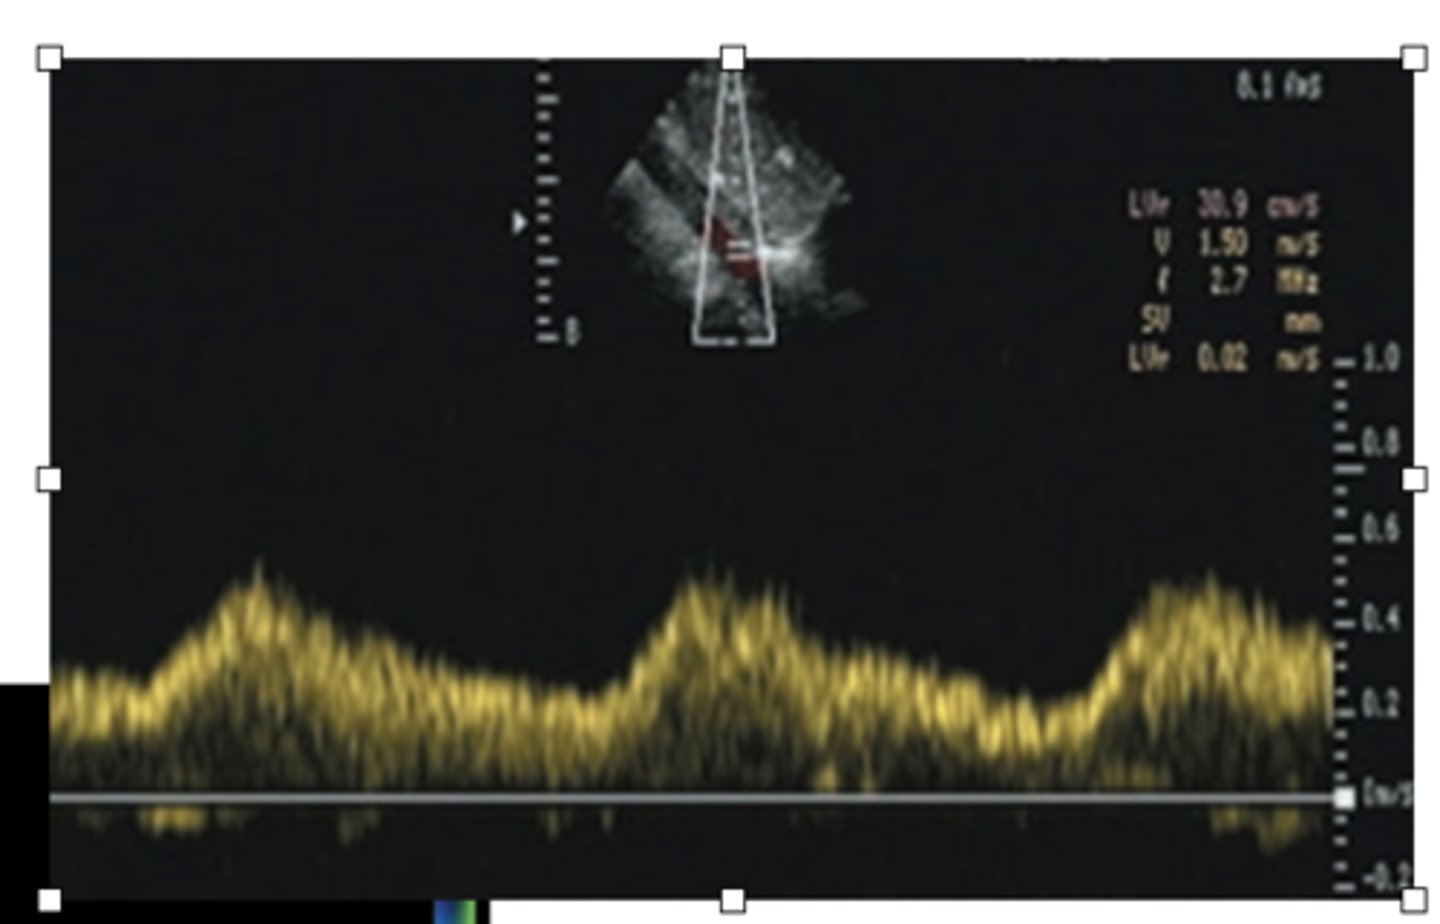

Aortic Stenosis

WHAT LESION?